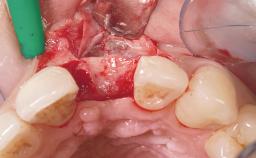

Late Placement of an Implant in a Maxillary Left Central Incisor Site

A 36-year-old female patient was referred for the replacement of the upper left central incisor (tooth 21), which had fractured. Although the tooth had been asymptomatic for many years, the crown began to loosen, at which time she presented to her dentist for an assessment. Teeth 21 and 22 had both been endodontically treated many years previously. She was a healthy individual and a non-smoker.

Bone Augmentation Horizontal|Staged

Soft Tissue Grafting Simultaneous

Bone Volume Deficient horizontally, requiring prior grafting